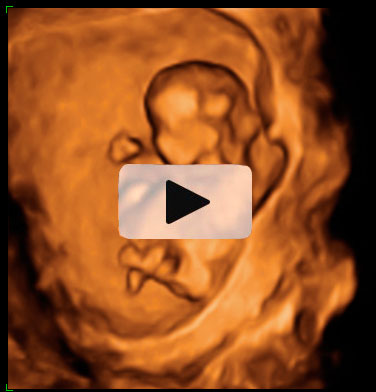

Ecografía semana 12 de embarazo gemelar

Ecografía 4D de gemelos de 12 semanas "contrapeados": Cada uno de los bebés está con la cabeza en una dirección, tal y como podemos visualizar en el ultrasonido. Uno de los gemelos se mueve al final de las imágenes de la ecografía mientras su hermano descansa.

Ecografía en 4D de gemelos de 12 semanas "contrapeados"

Cada gemelo está con la cabeza en una dirección, tal y como se aprecia en esta ecografía en 4D. Los dos fetos "contrapeados" tienen bolsas y placentas independientes. Destaca el movimiento del gemelo que aparece en la parte superior de la imagen: pareciera que se "arranca" a bailar al final del vídeo, mientras que su hermano permanece más tranquilo en su bolsa.